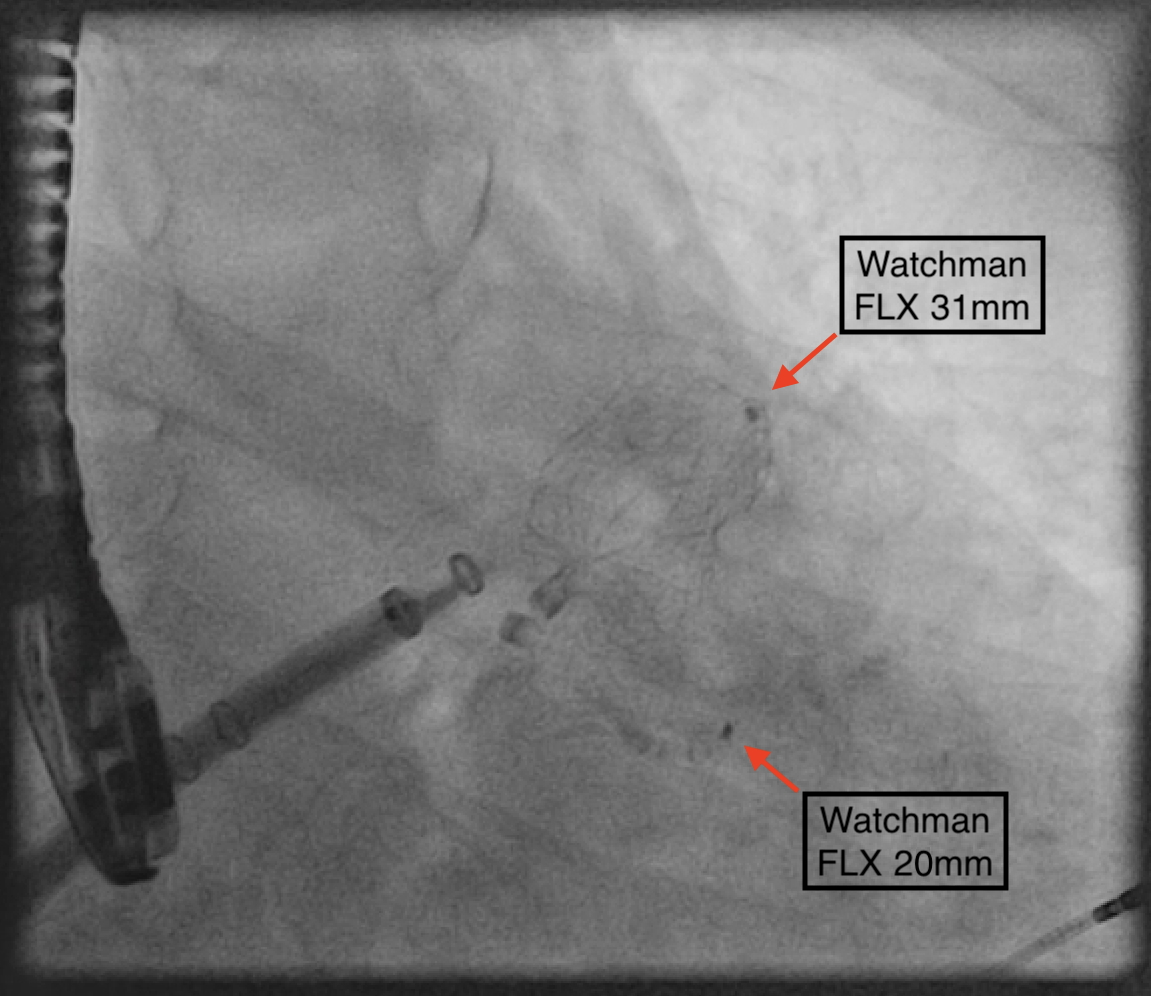

As there were no suitable alternative devices available, it was decided that a dual device closure strategy would be feasible, given the residual ostial diameter of 10 mm in the posterior lobe. Using a sequential single-sheath strategy, the 31-mm WATCHMAN FLX was deployed in the larger anterior lobe. Subsequently, a 20-mm WATCHMAN FLX was delivered, positioned, and unsheathed on the first attempt. Both devices were stable in a kissing arrangement in the LAA (Figure 2), with reassuring TOE images (Figure 1B).